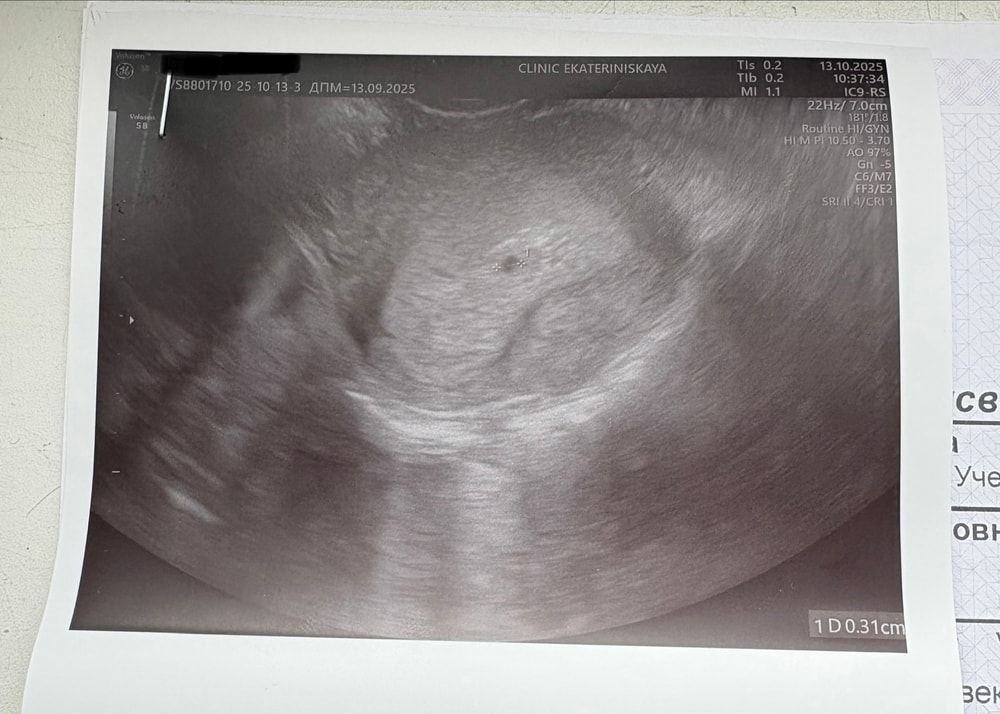

вчера у меня был срок 4+2, пошла на узи, чтобы исключить внематочную, хотя сомневалась, что увидят так рано. но бусинку увидели) и сказали, что через неделю можно прийти послушать сердечко. так вот, разве это не слишком рано? я в этом новичок, не сильно разбираюсь, но разве на 5 неделе его можно услышать? правда у меня и хгч довольно быстро вырос, на 15 дпо (примерно) был 1004.8, может мы как-то опережаем срок? извините, если глупости спрашиваю. всем добра🥰

Я ходила на узи в 6+3 (акушерских), по узи показывало 4+2 эмбриональных (от зачатия). Был только желточный мешок 2.2мм, плодное яйцо 7мм. А через 6 дней после этого узи сходила на другое, то есть срок акушерский был 7+2 (5+1 от зачатия) и там уже билось сердечко